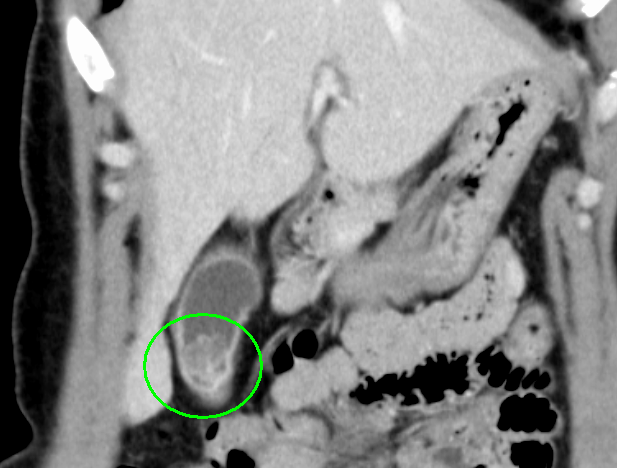

検査画像

CT画像